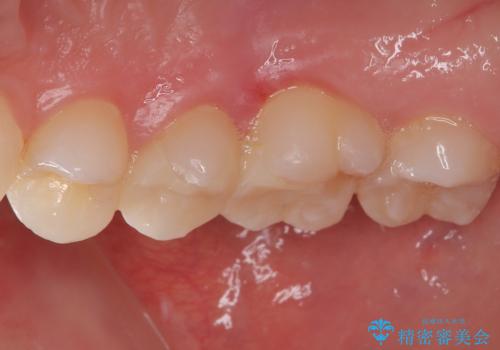

見た目、機能面共に大変喜んでいただきました。

歯と歯の間の虫歯をコンポジットレジンや保険のメタルインレーで治すと段差ができたりして清掃性が悪くなるので、セラミックインレー修復やゴールドインレー修復などの適合の良い詰め物で治療することをオススメします。